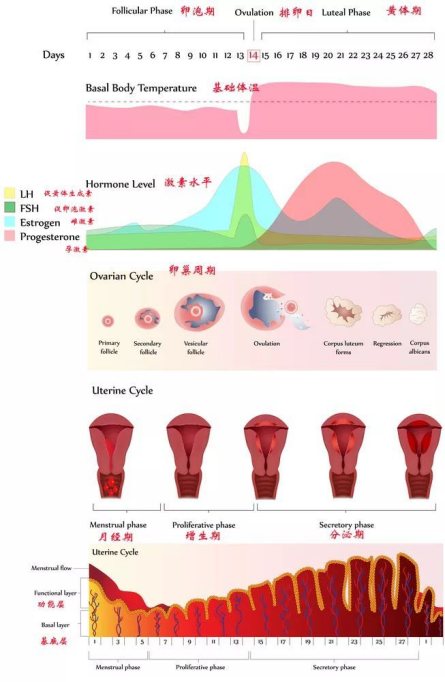

什么是排卵期和排卵日?

女性每个月卵巢都会排出一枚成熟的卵子,其具有一定的规律性,对于大多数有规律月经的女性来说,如果月经周期在28-30天左右的话,那么下次来月经前的第14天就是我们说的排卵日,在这一天的前5天和后4天,再加上这一天,一共十天的时间被称为是排卵期,在这期间内同房将会大大的提高受孕几率。

测量基础体温判断排卵期

女性基础体温有周期性变化,月经后半周期若基础体温升高能提示已排卵。正常情况下排卵后体温上升0.3-0.5℃,称双相型体温。如无排卵,体温不上升,整个周期间呈现低平体温,称单项型体温。

观察宫颈粘液推断排卵期

月经干净后,随着雌激素水平不断增高,至排卵期粘液分泌量增加,粘液稀薄、透明,拉丝度可达到10cm以上,类似蛋清一样,出现这种粘液的最后一天±48小时之间是排卵。